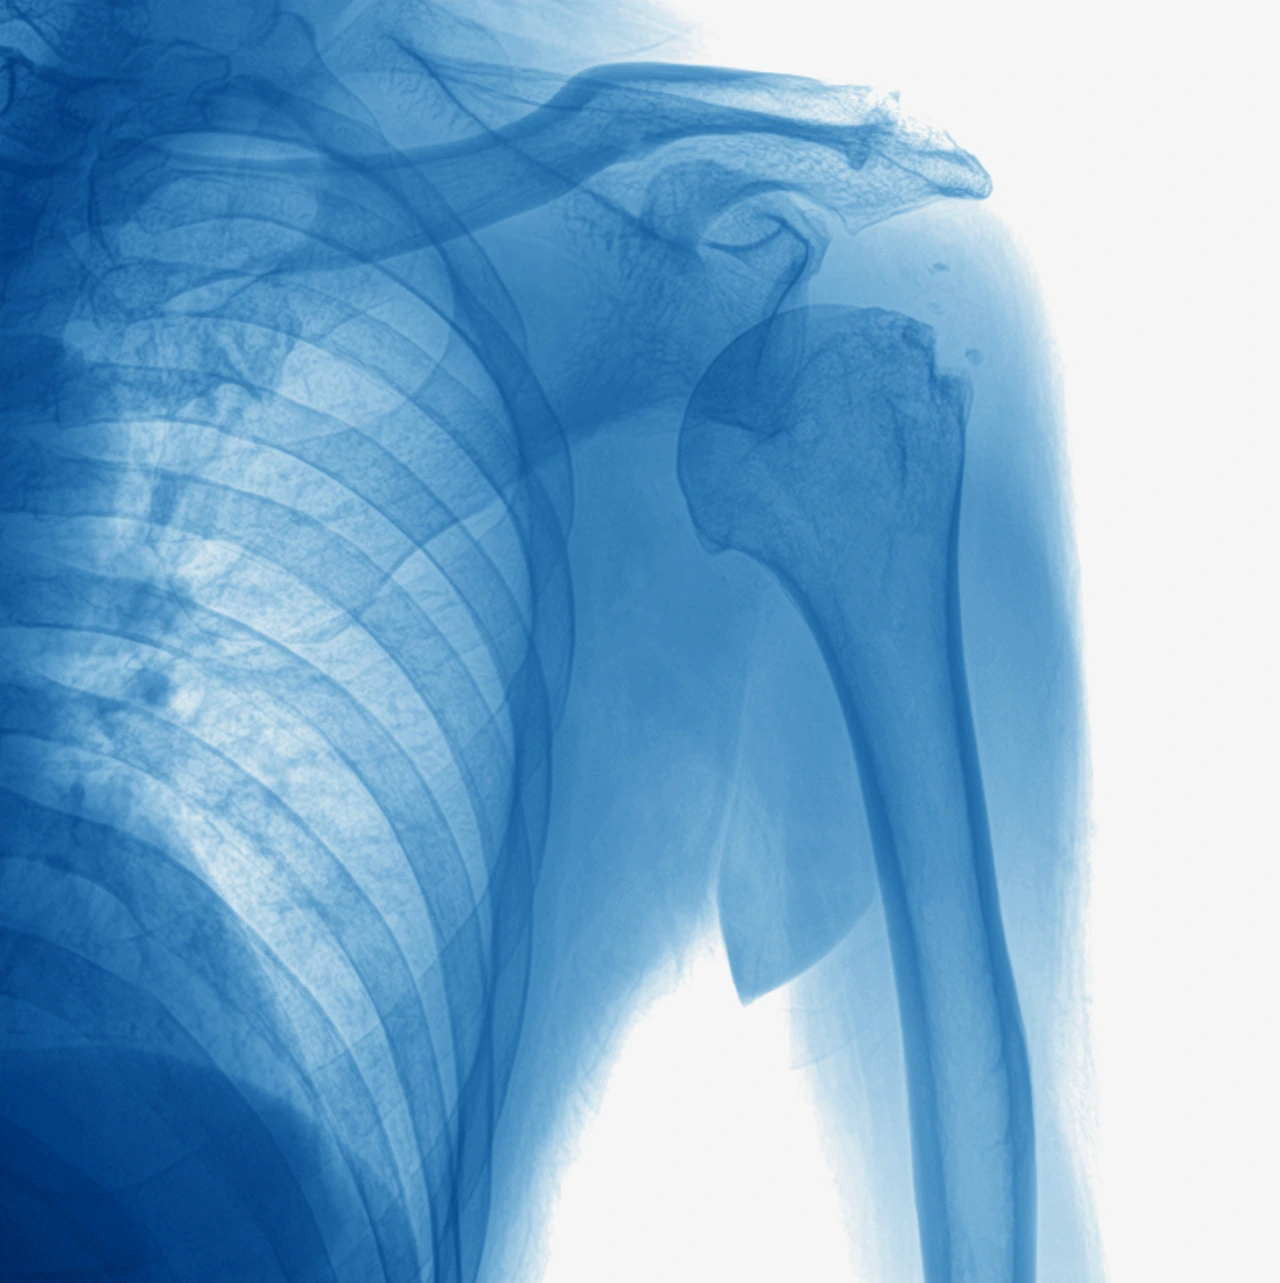

Additionally, imaging studies such as X-rays, computed tomography (CT), and magnetic resonance imaging (MRI) are necessary to determine the severity of the dislocation and to confirm or rule out adjacent injuries.